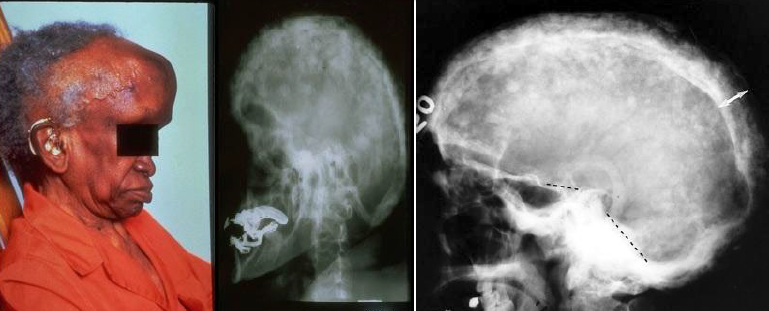

osteosarcoma

a malignant tumor of bone-forming tissue

most common primary malignant tumor of bone in patients under 40 years of age

gnathic

extragnathic

treatment: surgery, adjuvant chemotherapy, radiotherapy

gnathic osteosarcoma

3rd and 4th decades

extragnathic osteosarcoma

long bones

10-20 year olds

osteosarcoma radiographic features

“sun ray” or “sun burst” appearance

widening of the PDL of involved teeth

sun-ray or sun-burst appearance

radiographically, osteosarcoma of the jaws may show